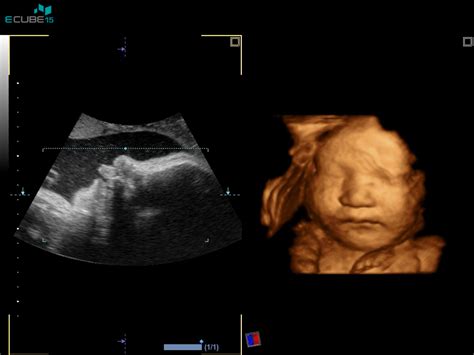

Morfologija ploda je natančen ultrazvočni pregled, ki se običajno izvede med 20. in 22. tednom nosečnosti. To je čas, ko je razvoj plodovih organov že v veliki meri zaključen, kar omogoča temeljito oceno. Cilj tega pregleda je potrditev normalnega razvoja ploda in odkrivanje morebitnih večjih razvojnih nepravilnosti.

- Obraz: V sagitalni (sredinski) ravnini se prikazuje profil obraza. Ocenjujejo se konica nosu, zgornja in spodnja ustnica ter bradica, ki naj bi bile v isti ravnini. Izmeri se lahko tudi dolžina nosne kosti. Pomembno je tudi oceniti razdaljo med očnicama (hipotelorizem ali hipertelorizem).